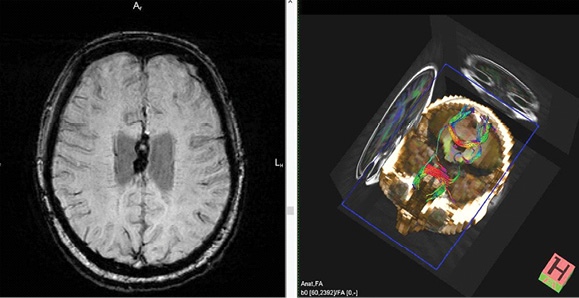

Рисунок 3. ДАП. Справа – изображения в режиме T2-ВИ. Аинтенсивный сигнал в проекции ствола мозолистого тела (отложения гемосидерина). Слева – ДТ МРТ. Разрыв комиссуральных трактов в области ствола мозолистого тела.

Figure 3. DAI. Right – images in T2-WI mode. Aintensive signal in the projection of the corpus callosum trunk (depositions of hemosiderin). Left – DT MRI. Rupture of the commissural tracts in the area of the corpus callosum trunk.

ДТ МРТ расценивает степень целостности проводящих путей, различие в миелинизации волокон, их диаметр. В основном определяют ход самых больших комиссуральных и проекционных трактов ГМ: мозолистого тела, кортикоспинальных трактов и волокон, проходящих через внутреннюю капсулу (рисунки 3

и 4) [2, 5, 9].

У лиц, перенесших дислокационный синдром со сдавлением ножки ГМ, в последующем формируется дегенерация волокон одного из кортикоспинальных трактов, что сопровождается развитием гемиплегии. ДТ МРТ у людей с ЧМТ используют для оценки динамики течения ДАП и в диагностике постдислокационных изменений [2]. При ДАП из-за дегенерации комиссуральных и восходящих нервных волокон через 3–4 месяца после ЧМТ фиксируется феномен «облысения» мозолистого тела, что представляется неблагоприятным прогностическим знаком восстановления сознания и психической деятельности [9, 24].